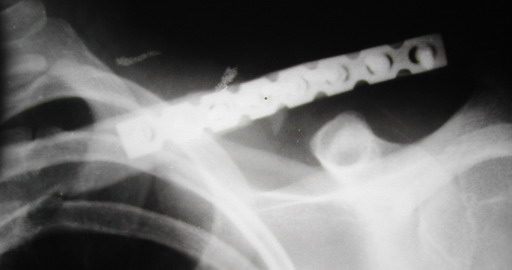

Во время стажировки в Австрии не мог не поинтересоавться, как австрийские хирурги лечат переломы ключицы. Оказалось, при переломах без смещения или с небольшим смещением накладывают восьмиобразную повязку, в остальных случаях выполняют остеосинтез пластинами.

Однако, чтобы уснуть с аппаратом внещней фиксации на ключице нужно "устать" не меньше, чем в рамке Чижина. К тому же, у некоторых больных присутсвует страх, что что-то в аппарате может раскрутиться, зацепиться за одеяло или подушку, или воспалиться. Крепко спят пациенты после качественного стабильного погружного остеосинтеза, когда ничего не торчит на коже. Особенно сладко спится после принятия душа или ванны. Это возможно после снятия швов. А вот у "чижиков" и "аппаратчиков" с полноценными водными процедурами определенные трудности.